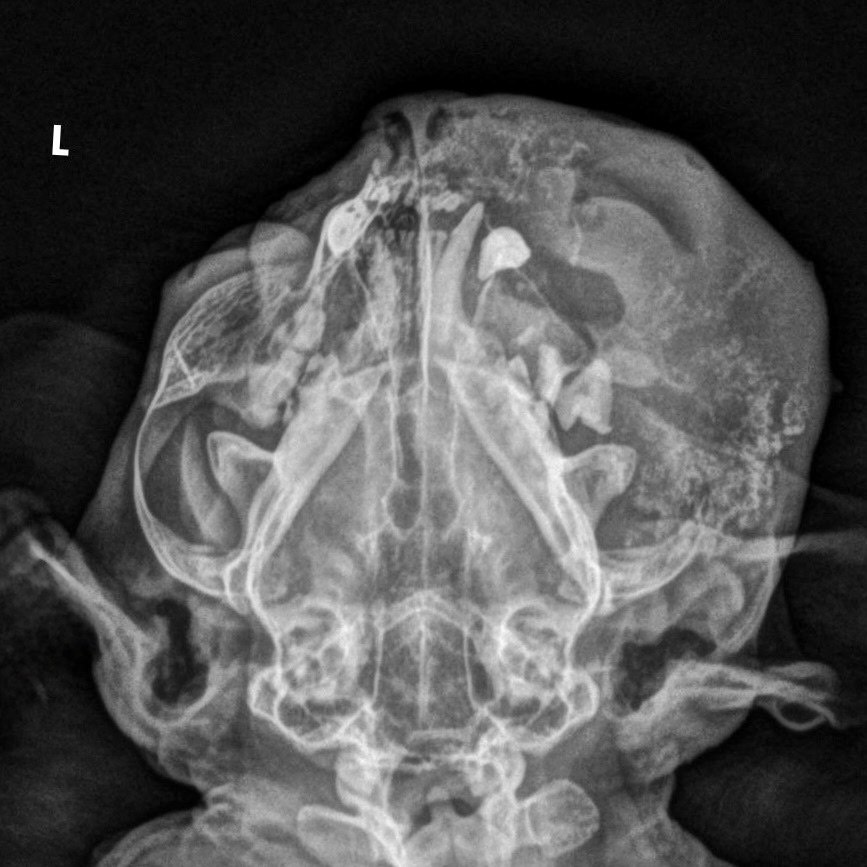

Тейковские ветеринары недавно помогли 13-летней собаке Стрелке. Огромное новообразование мешало пожилой собачке ходить. На осмотре у собаки выявили 2 паховые грыжи. Чтобы убрать их, хватило одной операции. Сейчас Стрелка чувствует себя хорошо и уже вернулась к прежней, активной жизни.

Другая история, увы, с печальным концом. Хозяева обнаружили у 16-летнего кота припухлость на щеку. Через 4 месяца обратились к ветеринару. Ситуация была очень запущенной, котику становилось все хуже, пришлось прибегнуть к эвтаназии.

Ветеринары просят хозяев быть внимательнее к своим питомцам. Любое изменение в их внешности или поведении – повод обратиться к специалисту. И как показывает практика, чем раньше это сделать, тем у собаки или кошки больше шансов на спасение.

Фото: ВетКэт – ветеринарная клиника Тейково / ВКонтакте